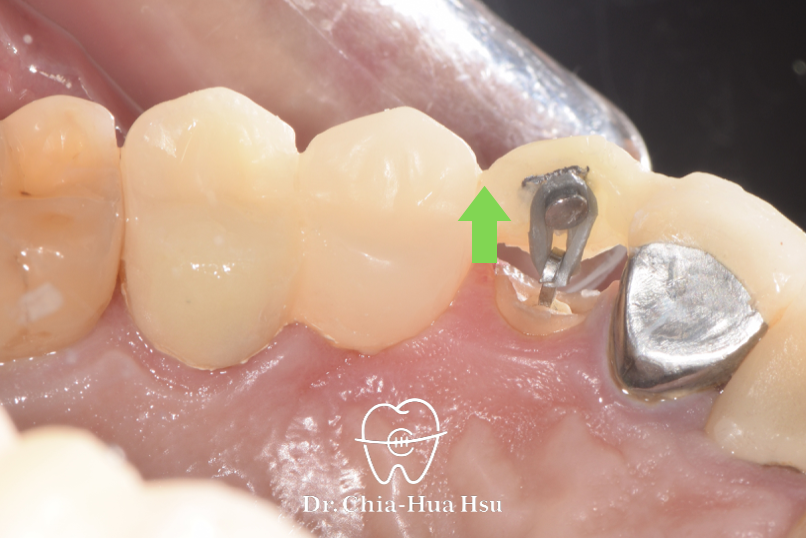

• 強逼萌出術 Forced eruption :在臨時牙橋上黏著金屬鈕扣,再使用橡皮圈把殘根牙齒拉出來以獲得足夠齒質(Ferrule effect),以利新的假牙製作。

治療中